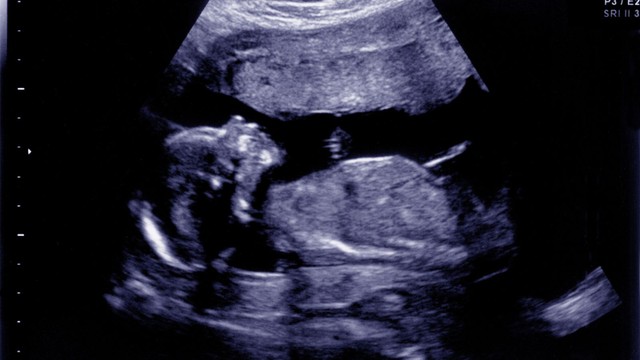

Hình ảnh siêu âm bé gái 16 tuần tuổi giúp ba mẹ theo dõi sự phát triển của thai nhi, đồng thời phát hiện sớm bất thường. Cùng tìm hiểu chi tiết trong bài viết sau!